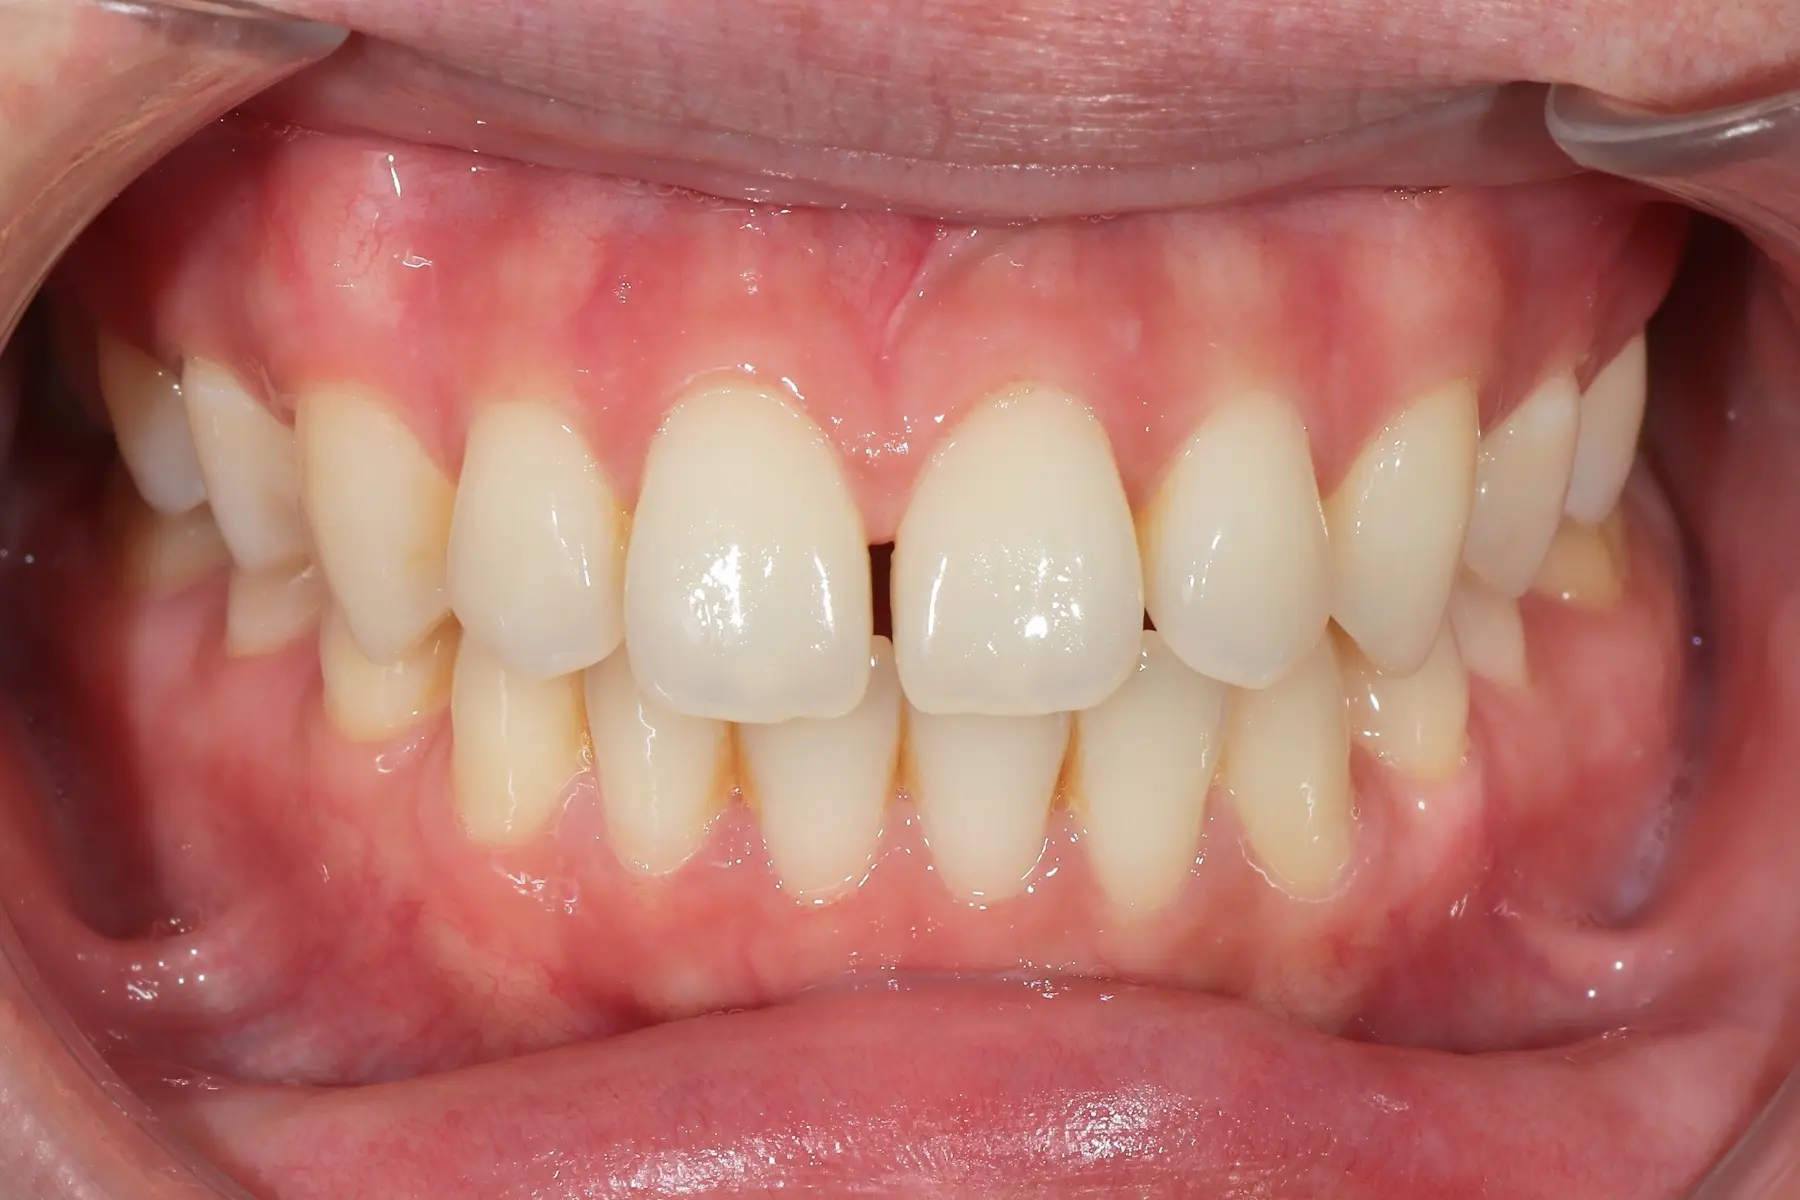

Dentist 陳昕 全口照護醫師 看診項目 前牙美學仿生樹脂補牙/全科牙醫 學經歷 臺北醫學大學牙醫系學士 前天主教新店耕莘醫院醫師 前臺北榮民總醫院醫師 亞洲齒列再生研究學會Advance植牙補綴專科訓練 微光私塾牙周雷射微創治療技術訓練 臺灣牙醫顯微美學治療學會會員醫師 中華審美牙醫學會會員醫師 CASE 案例分享 滲透型樹脂修復 主治醫師 陳昕 治療時間 單次療程 主訴 想處理前牙白白的色斑 前牙美學/仿生美學樹脂 主治醫師 陳昕 治療時間 單次療程 主訴 牙齒整齊,但門牙中間縫隙明顯,影響笑容美觀 前牙美學/陶瓷貼片 主治醫師 陳昕 治療時間 約1個月 主訴 兩顆門牙缺角,想要重建外觀 前牙美學/滲透型樹脂修復 主治醫師 陳昕 治療時間 單次療程 主訴 門牙有長期存在的白斑與表面不平整,影響外觀與自信 前牙美學/仿生美學樹脂 主治醫師 陳昕 治療時間 約兩週 主訴 矯正後的黑三角縫問題 前牙美學/仿生美學樹脂 主治醫師 陳昕 治療時間 約三週 主訴 因牙周病產生的黑三角縫 前牙美學/牙冠增長術、仿生全瓷牙冠 主治醫師 陳昕 治療時間 約6個月 主訴 牙齒排列不整、假牙外觀不自然 前牙美學/仿生美學樹脂 主治醫師 陳昕 治療時間 約兩週 主訴 露齒笑時黑三角縫明顯,覺得不好看 前牙美學/仿生美學樹脂+噴砂美白 主治醫師 陳昕 治療時間 約兩週 主訴 露齒笑時有不好看的黑三角縫,容易有茶垢沉澱,讓縫隙更明顯 牙齒美白/噴砂美白+冷光美白 主治醫師 陳昕 治療時間 單次療程 主訴 前牙泛黃且染色明顯,影響外觀與自信 牙齒美白/噴砂美白 主治醫師 陳昕 治療時間 單次療程 主訴 牙齒表面有喝咖啡、抽菸造成的外部染色,影響外觀與自信 點此載入更多 Column 精選文章 FEATURED 精選案例 【牙科修復案例】陶瓷貼片可以做一顆嗎?單顆門牙缺角修復,陶瓷貼片重建自然笑容 2026-01-16 從「假笑」到「自然笑容」的轉變——認識「牙冠增長術」與「仿生全瓷冠」 2025-10-14 Video 精選影音